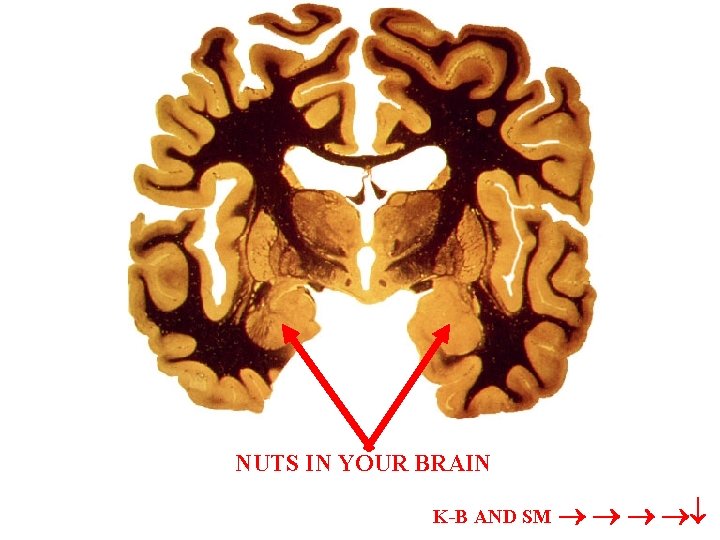

NUTS IN YOUR BRAIN K-B AND SM

KLUVER BUCY SYNDROME TAME-no display anger or fear VISUAL AGNOSIA oral compulsions may provide alternate means of object identification HYPERPHAGIC HYPERSEXUAL RECENT MEMORY DEFICIT “Emotional Blunting”

bilateral lesions=Urbach-Wiethe disease=patient SM; insensitivity to the intensity of fear shown by face; hyaline-like deposits skin, muc. memb. does not show autonomic fear responses to arousing stimuli fear learing is lost her memory was not enhanced by emotionally arousing pictures no uneasy feeling about someone who is in fact predatorial; does not recognize fear in herself; does not evince normal facial expressions in fearful situations can’t tell negative emotions expressed by other people. Because she often fails to recognize criticism or aggression, S. M. has difficulty interacting socially. Fear conditioning